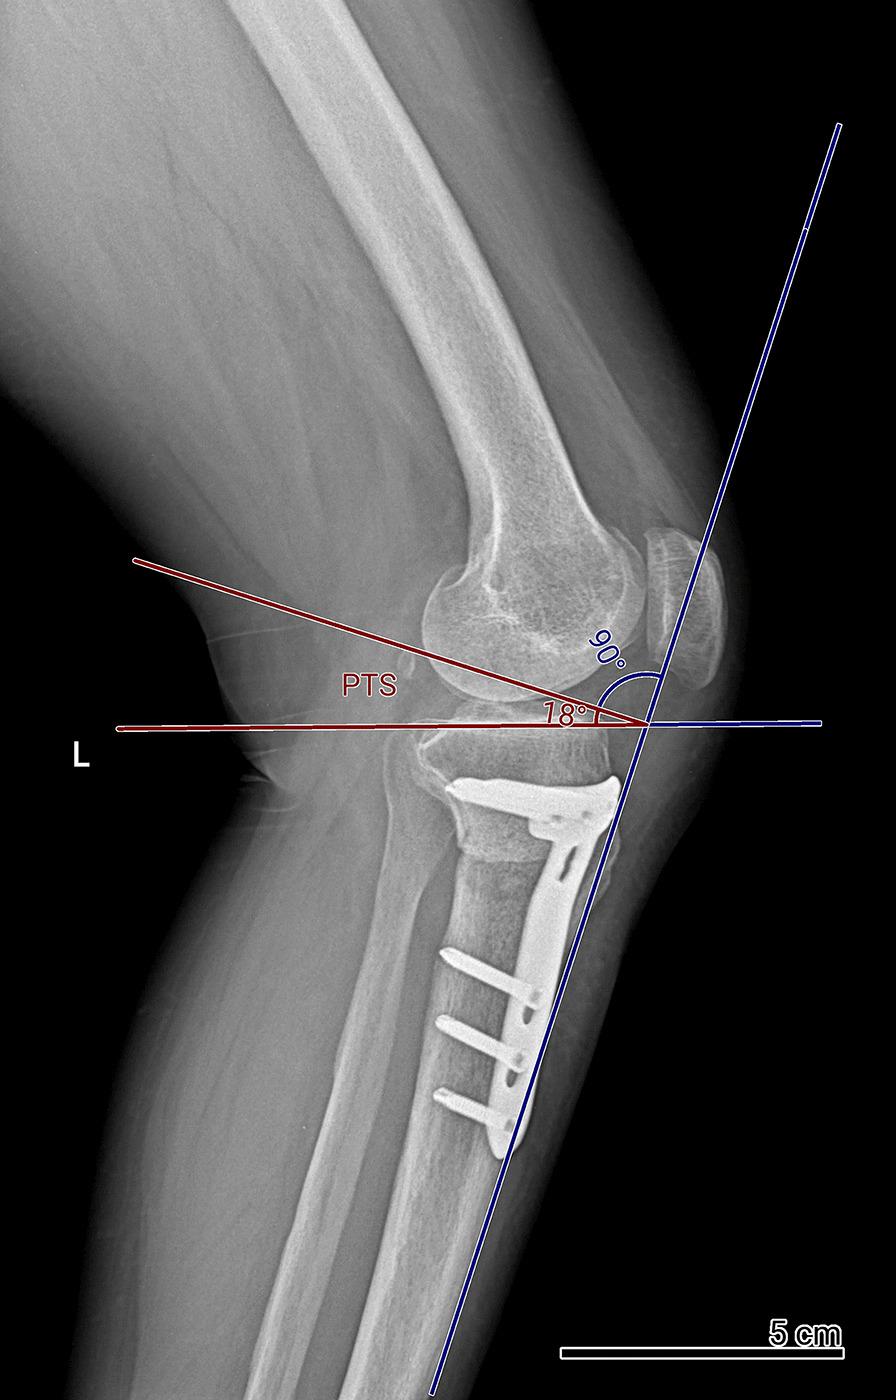

Posterior tibial slope (PTS) alterations following open-wedge high tibial osteotomy (OWHTO) can cause instability and excessive tibial translation in the sagittal plane. These changes can be influenced by the type of fixation. This study aims to compare PTS changes between patients undergoing OWHTO with Puddu plate or TomoFix plate fixation.

In this retrospective cohort study, we included 104 knees from 85 patients undergoing OWHTO, with a mean age of 41.98 ± 9.95 years; 51.8% of the participants were male. Seventy-two knees were fixed with Puddu plates, while 32 knees were fixed with TomoFix plates. PTS changes, demographic factors, Cincinnati Knee Rating Score (CKRS), Tegner-Lysholm score (TLS), length of stay (LOS), and complications were evaluated. PTS changes were measured preoperatively, immediately postoperatively, and at the 6-month follow-up.

Demographic factors were similar between the Puddu plate and TomoFix groups. There were no significant differences in preoperative, postoperative, or follow-up PTS measurements between the two groups. PTS changes were not significant in the TomoFix group postoperatively or at follow-up. However, the Puddu plate group showed a significant increase in PTS both postoperatively (P = 0.027) and at follow-up (P = 0.014). CKRS, TLS, LOS, and complications did not significantly differ between the groups.

While overall PTS changes did not significantly differ between the Puddu Plate and TomoFix Plate groups, analyzing changes within each group revealed distinct results. TomoFix fixation exhibited nonsignificant PTS changes, while Puddu plate fixation resulted in a significant increase in PTS after surgery and at the 6-month follow-up. Our findings suggest that the choice of fixation may influence PTS changes after OWHTO.